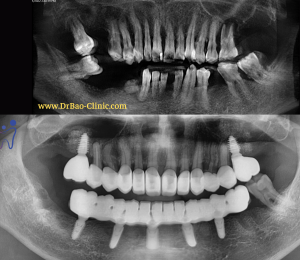

Xray show many infection around upper teeth

Radiograph after surgery 1 day

Radiograph after loading final prosthetic

CT Xray after 22 months loading: stable bone around implant, no inflamation